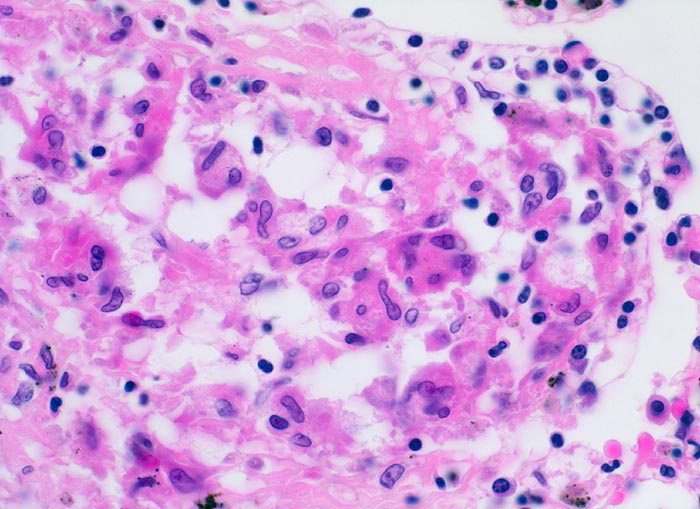

Sarkoidosegranulom

Systemerkrankung/Immunpathologie

Lunge

Produktives, nicht nekrotisierendes Granulom mit zahlreichen Epitheloidzellen, Riesenzellen vom Fremdkörpertyp und einem peripheren Saum von Lymphozyten und einzelnen Plasmazellen.

In Spezialfärbungen lassen sich weder Pilze noch Bakterien nachweisen.

400